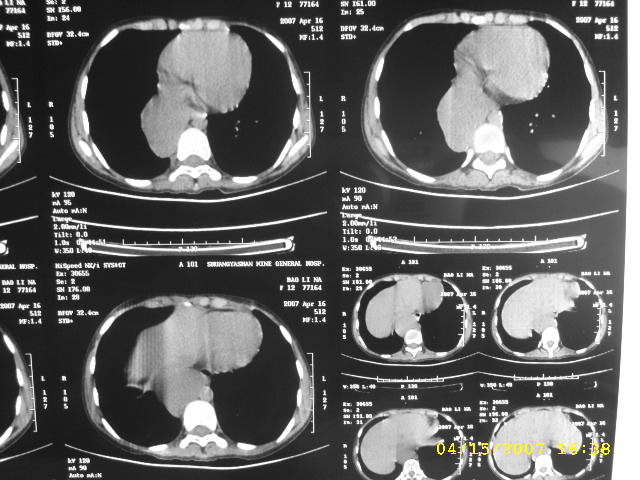

女,12,后纵隔占位十余年。

女,12,后纵隔占位十余年,没什么特异性,考虑1纵隔囊肿2肺隔离症3神经源性肿瘤,建议增强

女,12,后纵隔占位十余年,没什么特异性,考虑:1 纵隔囊肿. 2 肺隔离症. 3 神经源性肿瘤,建议增强

女12岁,发现占位十余年,首先考虑是先天性病变:

食管囊肿

神经源性肿瘤